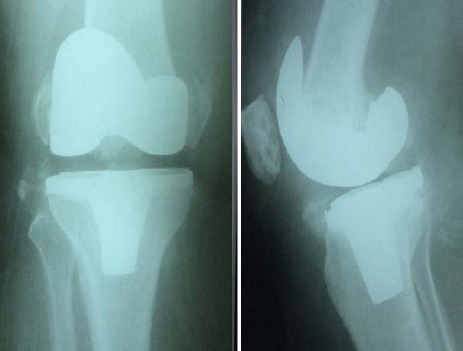

Figure 8.

Post operative radiographs after revision arthroplasty using a constrained prosthesis and metaphysial cone.